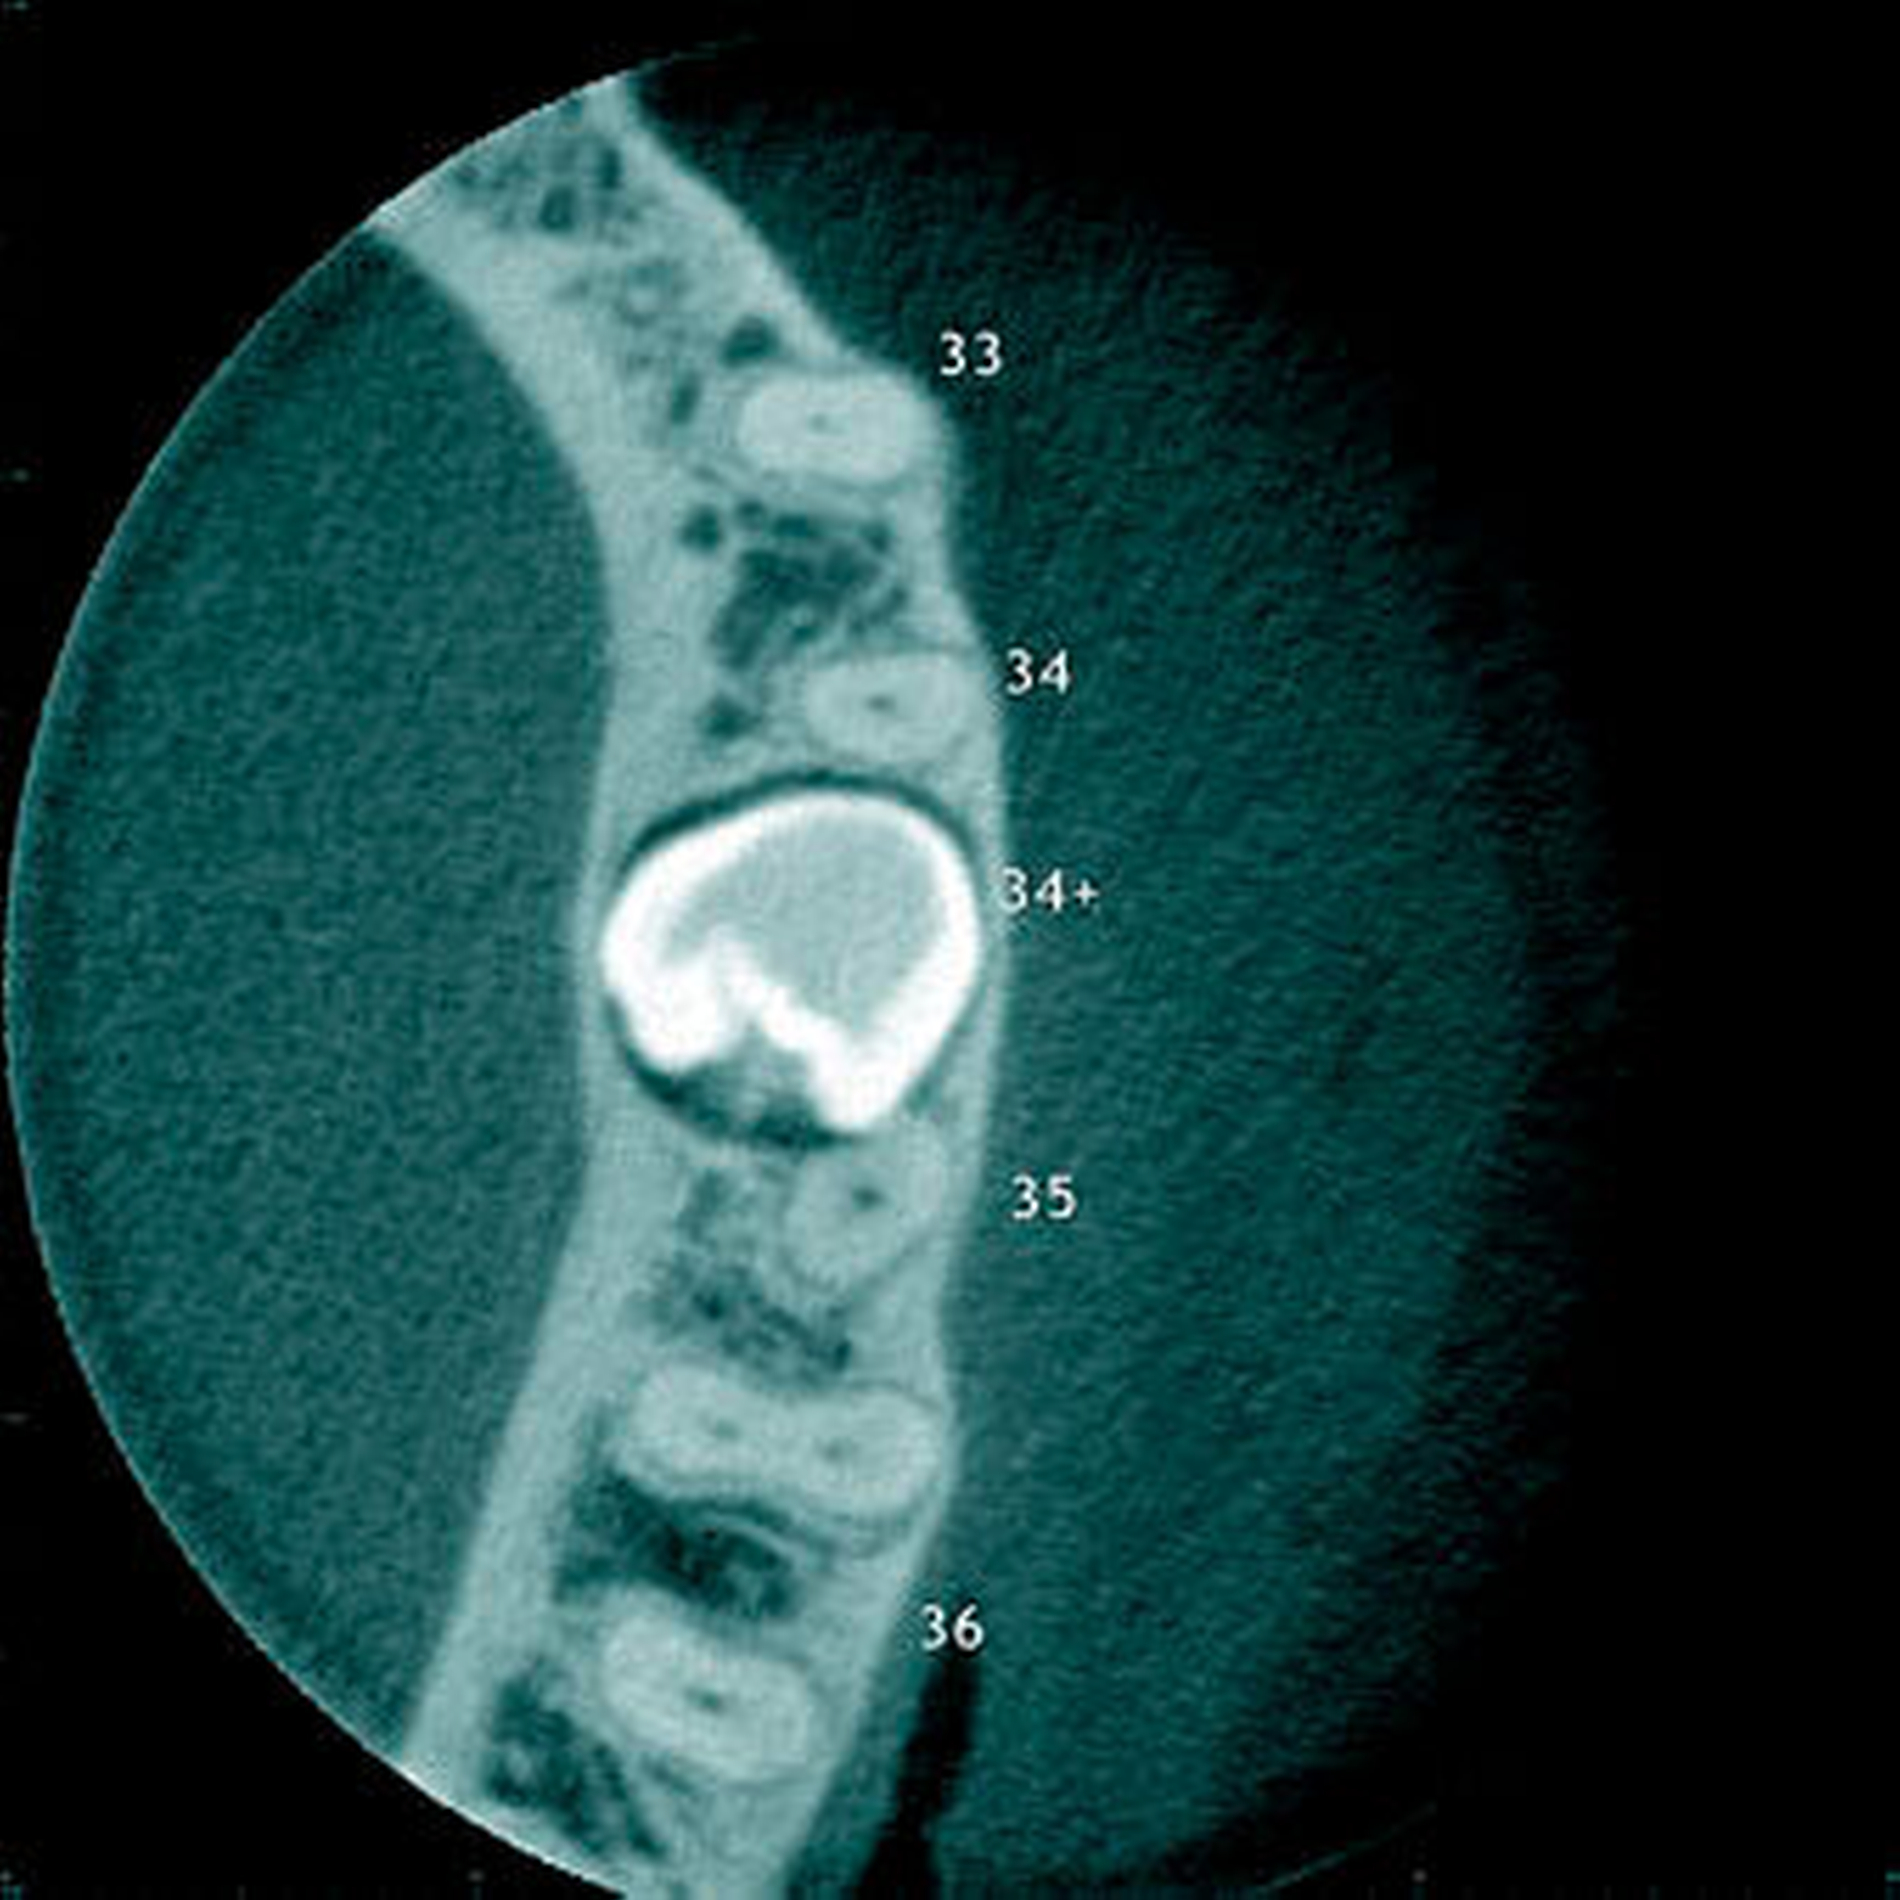

Radiologisch erscheint der Zahnfollikel um retinierte überzählige Zähne als eine dünne perikoronale Radio-luzenz, welche in der Regel nicht breiter als 3 mm ist [Mossaz et al., 2014] (Abbildung 19). Andere Autoren betrachten eine Breite von 2 mm als physiologisch [Tyrilogou et al., 2005]. Bis heute fehlen aber klare Angaben zu den normalen Dimensionen des Zahnfollikels, das heißt, es ist radiologisch nicht eindeutig zu erkennen, wann ein zystischer Prozess vorliegt [Villalba et al., 2012]. Studien berichteten über eine (pathologische) Erweiterung des Follikularraums in 1,4 Prozent bis 5,3 Prozent der überzähligen Zähne [von Arx 1990; Tyrologou et al., 2005; Liu et al., 2007; Hyun et al., 2009; Mossaz et al., 2014]. Dagegen sahen Koch und Mitarbeiter (1986) bei 54 überzähligen Zähnen keine Erweiterung des perikoronaren Raumes während des Beobachtungsintervalls (Mittelwert: 7,3 Jahre).

Überzählige Zähne können einzeln oder multipel auftreten [von Arx, 1990; Rajab Hamdan, 2002; Fernández Montenegro et al., 2006; Liu et al., 2007; Gündüz et al., 2008; Ferrés-Padró et al., 2009; Hyun et al., 2009]. Einzelne überzählige Zähne treten in 65,8 bis 80,5 Prozent, doppelte in 14,5 bis 27,7 Prozent und multiple in 0,6 bis 8 Prozent der Fälle auf [Rajab Hamdan, 2002; Fernández Montenegro et al., 2006; Liu et al., 2007; Ferrés-Padró et al., 2009; Hyun et al, 2009; Mossaz et al., 2014]. Einzelne oder doppelte überzählige Zähne finden sich typischerweise in der Oberkieferfront [Rajab Hamdan, 2002; Fernández Montenegroet al., 2006; Mossaz et al., 2014]. Multiple überzählige Zähne werden vor allem im Prämolarenbereich des Unterkiefers gefunden [Abbildung 4; YUSOF 1990, Ferrés-Padróet al., 2009; Wang Fan, 2011]. Multiple überzählige Zähne sind zudem oft mit anderen Erkrankungen oder Syndromen assoziiert, dazu gehören Lippen-Kiefer-Gaumenspalten, die cleidokraniale Dysplasie oder auch das Gardner-Syndrom. Bei Patienten mit einer Lippen-Kiefer-Gaumenspalte wird vermutet, dass sich die überzähligen Zähne aus der Fragmentierung der dentalen Lamina bei der Spaltbildung ergeben [Garvey et al., 1999; Wang Fan, 2011].